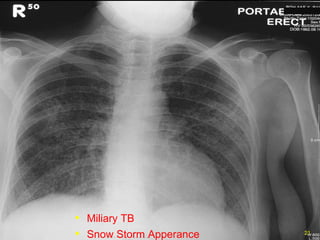

Miliary TB Snow Storm Apperance